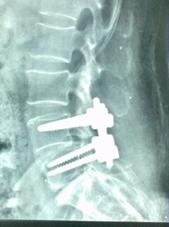

颈椎间盘突出、颈椎管狭窄——开展颈椎前路、后路手术治疗颈椎间盘突出、颈椎管狭窄,解除许多患者病痛,通过网上会诊方便患者,在家就能得到著名脊柱外科专家王少波教授诊治。

1).C4/5、C5/6间盘突出术前、 术后(C5椎体次全切除,钛笼植入)

2). C5-C6间盘突出术前、 术后(间盘切除,Cage植入)